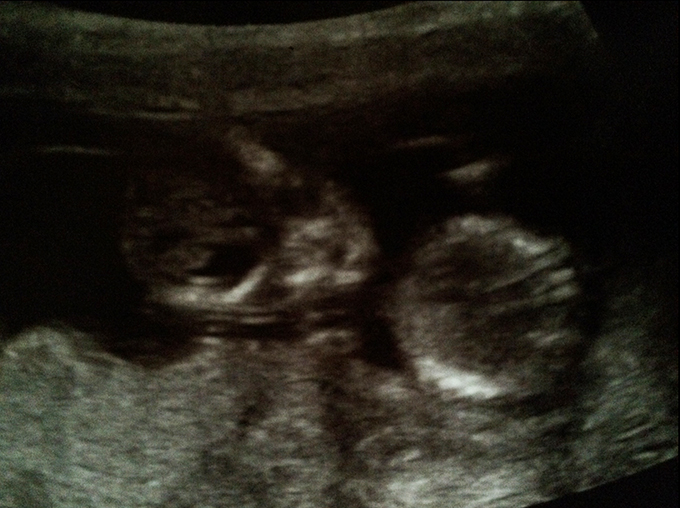

Here are my ultrasound pics. The baby measured 12wk 4days, so I'm not sure if it's still too early to say anything. I would love to have a video for you to show, but I only got some pics. I saw a clear fork several times, but it was difficult for me to see the angle because the baby was moving all the time and looked curled. I saw this kind of fork (these are not from my pics):

Unfortunately I didn't get any pics to take home where "the fork" was showing, and I'm not sure if any of these are actually nub pictures. I can't tell... I don't know if what you see on pic 2 is a nub, because to me it starts quite high. But it is angled if it's a nub. I still get a feeling it's a boy, because I can't see any girl signs either. Can you?